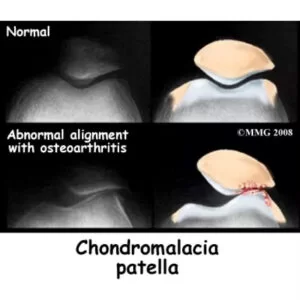

مسیر تشخیص کندرومالاسی کشکک

– شرح حال و معاینه فیزیکی

– MRI برای بررسی وضعیت غضروف

– تصویربرداری ساده جهت رد سایر مشکلات ساختاری زانو